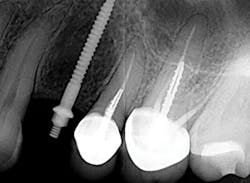

Figure 9: Implant placement

A 1.8 mm x 14 mm Anew implant (Dentatus) was selected, and a surgical guide was fabricated for a flapless approach. In this instance, a healing cap was placed, and the existing flipper was relieved to address financial concerns (figures 9 and 10). A screw-retained crown was fabricated three months post insertion (figures 11 and 12). The patient reported no postoperative discomfort, and the case remains successful, as shown in the two-year postoperative x-ray (figure 13).